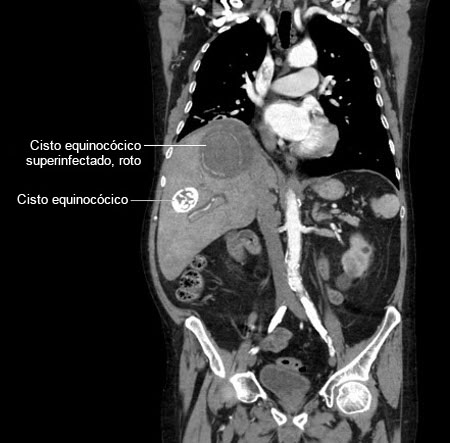

Abscesso hepático: tomografia computadorizada (TC) mostrando um cisto equinocócico rompido e infectado de 8 cm por 8 cm e um cisto equinocócico de 4 cm por 4 cm em um homem de 69 anos de idade, que apresentou hipotensão e dor torácica com irradiação para a região epigástrica

Do acervo de imagens radiológicas do Massachusetts General Hospital (MGH)